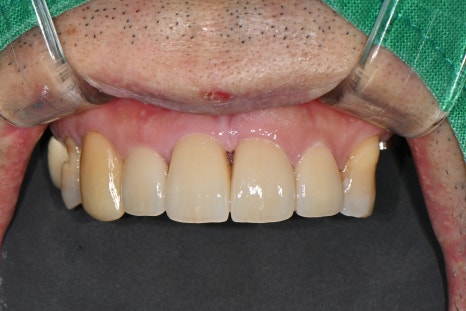

신경치료를 마친 앞니는 원내 기공사와 협업하여 심미 보철로 마무리했습니다.

기존 치아와 거의 차이가 없을 정도로 자연스러운 색상과 형태로 제작되었고,

웃을 때에도 전혀 티 나지 않아 환자분도 매우 만족해하셨습니다.

🖼️ 앞니 최종 보철 사진

최종 보철 장착 후 정면 사진